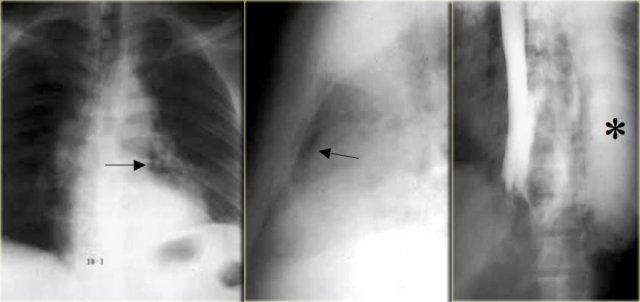

Hình ảnh này thuộc về một bệnh nhân mắc hội chứng Boerhaave.

X-quang ngực cho thấy tràn khí trung thất (các mũi tên).

Chụp thực quản cản quang cho thấy thuốc cản quang tan trong nước thoát ra ngoài lòng mạch ở nửa ngực trái (dấu hoa thị).

Thủng hầu như luôn xảy ra ở phía trái của thực quản đoạn xa.

X-quang cho thấy khí trung thất, tràn dịch và sau đó là tràn khí màng phổi.

Chụp thực quản cản quang được sử dụng để xác nhận rò rỉ, trước tiên dùng thuốc cản quang tan trong nước, sau đó dùng barium nếu không phát hiện rò rỉ.

Bên trái là hình ảnh một bệnh nhân mắc hội chứng Boerhaave.

Chụp thực quản barium cho thấy khí ngoài lòng thực quản (mũi tên) mà không có thuốc cản quang thoát ra ngoài.

CT cho thấy khí ngoài lòng thực quản (các mũi tên).

Vết rách ở thực quản đoạn xa bên trái được xác nhận trong phẫu thuật.

CT có thể phát hiện lượng nhỏ khí ngoài lòng thực quản hoặc thoát thuốc cản quang mà không thể nhìn thấy trên X-quang hoặc chụp thực quản cản quang.